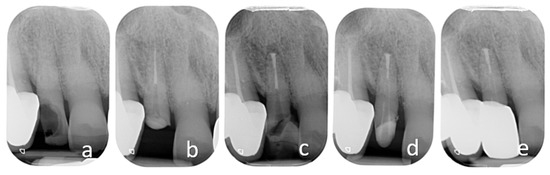

4.2. Surgical Extrusion

4.2.1. Advantages

4.2.2. Disadvantages

4.2.3. Complications